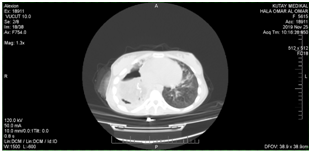

Female Patient (PT) 15 years old, referred to our hospital after more than 6 months of recurrent infections in right lower lobe (RLL) of the lung Figure A1 & A2. The PT had investigated, CXR was done Figure A3. The sputum was negative for TB many times. Bronchoscopy was done, no foreign body, no tumor, no anomalies, the washing was tested for TB and was negative. The decision for surgery was taken, the RLL was contracted, nodular and solid. RL Lobectomy was done. At second day post operation the PT had fever, sweat, no appetite and bad general condition. CXR revealed bilateral diffuse infiltrations. Figure B1. We decided to give her a trial TB treatment. After five days PT began to respond clinically. So TB treatment for minimum 6months is ordered.

A1 22-1-2019

A2 6-2-2019

A3 19-6-2019